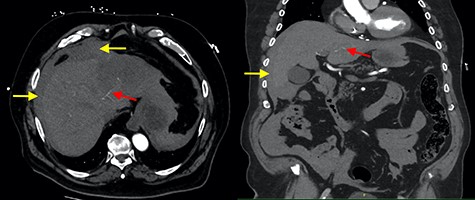

He was hypotensive (systolic 60Â mmHg) with a grossly distended abdomen that was tender to palpation in all quadrants with associated guarding and localized peritonism in the right upper quadrant. A bedside ultrasound of the abdomen suggested a peri-hepatic collection. After initial resuscitation, haemodynamics improved and the decision was made to perform a computer tomography (CT) angiogram to identify a bleeding source. This confirmed a peri-hepatic collection predominantly located around the left lobe of the liver with contrast extravasation from a prominent vessel extending towards the liver capsule (Fig. 1). Resuscitation continued with the activation of a massive transfusion protocol. Prothrombin concentrate and tranexamic acid were administered to partially reverse rivaroxaban, after coagulation studies revealed an international normalized ratio (INR) of 6.7. A Child-Pugh score of 9 (Class B) was calculated, placing the patient at a 30% risk of peri-operative mortality.

Axial and coronal contrast images of abdomen (yellow arrow—haemoperitoneum, red arrow—contrast extravasation from segment II/III artery).